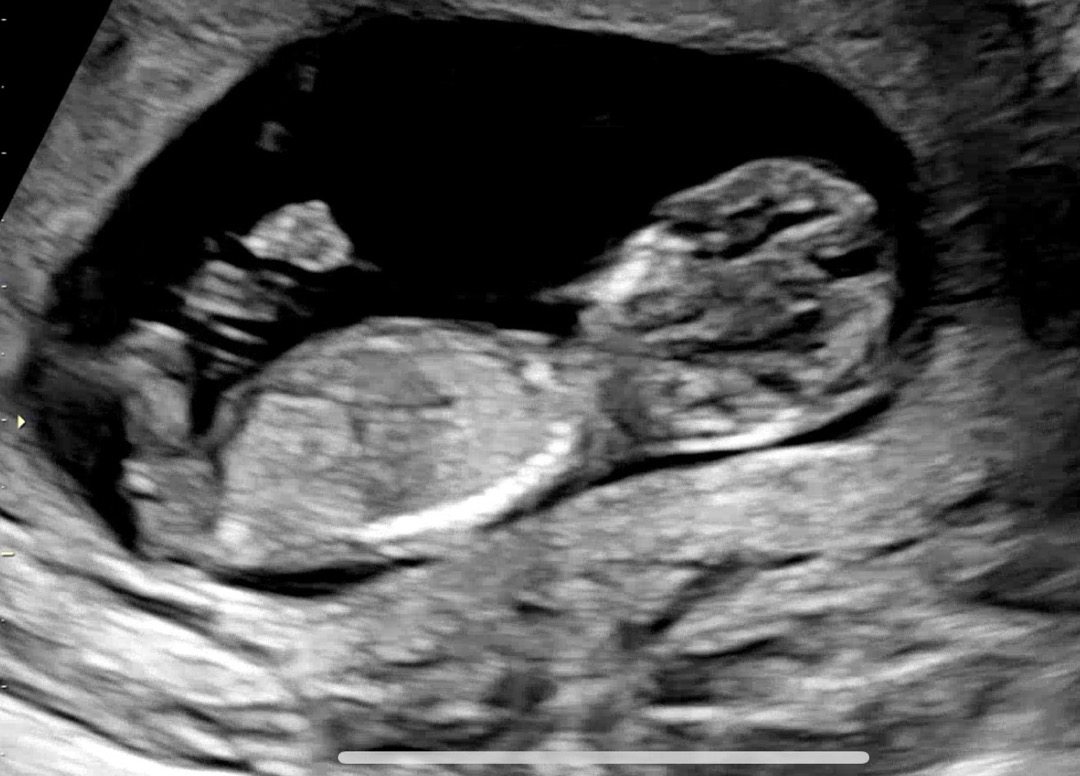

11주 6일차 초음파인데 성별 너무 궁금해서요🤭 다음예약이 16주차라 기다리기 힘드네요!!